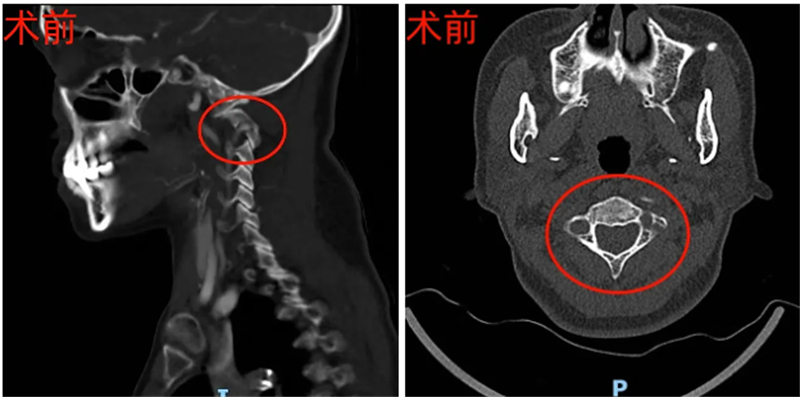

53岁的韦女士长期饱受反复后颈部剧痛和肢体麻木折磨,生活质量大打折扣。经检查评估,韦女士被确诊患有极其凶险的寰枢关节脱位、颅底凹陷症并脊髓受压,意味着连接头颅与颈椎的关键“生命中枢”正遭受严重压迫,如不及时有效干预,可能导致瘫痪甚至危及生命。

本次手术面临三大核心难点:需将脱位的寰枢椎准确复位,毫米级偏差或力度不当就可能损伤脊髓、延髓,风险极高;患者属“难复性脱位”,狭小的寰枢椎侧块关节间隙被瘢痕、骨赘填充粘连,需在有限空间内精细松解,堪比“悬崖微雕”;且存在双侧椎动脉高跨,如同手术通道上的“高压线”,术中操作稍失误就可能损伤椎动脉,引发致命大出血或脑干梗塞。